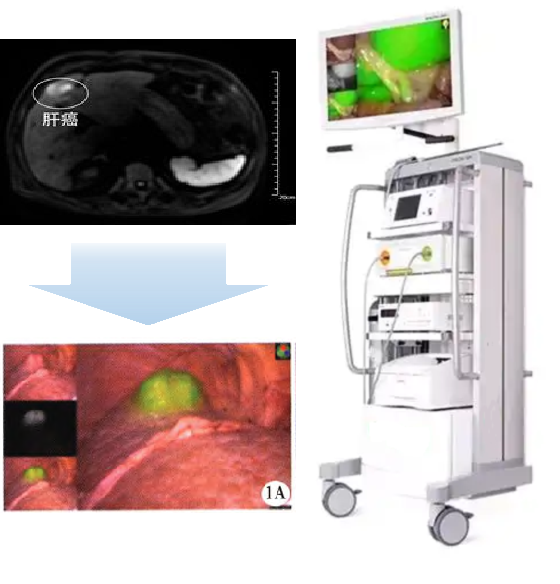

《国民经济和社会发展第十四个五年规划和2035年远景目标纲要》专栏4提到:“突破高端医疗设备核心技术、突破腔镜手术机器人、体外膜肺氧合机等核心技术,研制高端影像、放射治疗等大型医疗设备及关键部件。” 普利制药的硼药项目正是与高端放射治疗医疗设备协同作业;同时新型造影剂项目亦与腔镜手术机器人相辅相成。

手术机器人手术的精准性依赖造影剂。普利制药自主研发的双模造影剂PL002是一种同时具有近红外荧光和MRI T1增强双重功能的小分子药物,主要用于实体瘤的诊断与术中导航。PL002的研制首次提出通过整合磁共振技术,弥补现有荧光染料假阳性率高、透射深度有限等的短板,进而提升手术的精确性,降低手术过程中的风险,是全球首个获批临床试验的荧光/磁共振双模态造影剂。

本项目已经获得美国FDA临床试验批件,预示着海南普利在造影剂领域的长期投入,并致力于开展独具特色的差异化国际化创新发展路径。